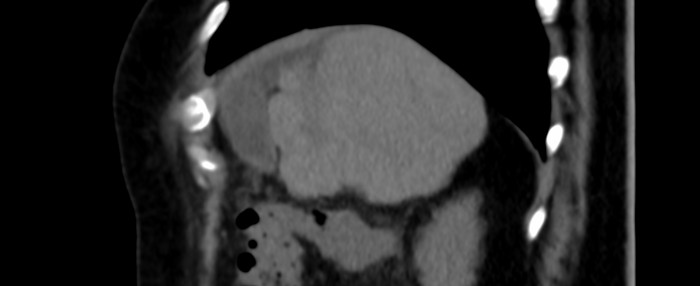

Presentamos el caso de un paciente con diagnóstico de cáncer de mama derecha triple negativo, para el cual se solicita estudio de extensión para estadificación. Se realizó tomografía (TC) de tórax y abdomen simple identificando la vesícula biliar de situación suprahepática (Figs. 1 y 2) asociado a hipoplasia del lóbulo derecho (Fig. 3), así como escaso líquido perivesicular (Fig. 4); no hay lesiones hepáticas que sugieran actividad metastásica. En el resto del estudio no se identificaron alteraciones, ni variantes anatómicas.

Figura 3

TC de abdomen corte sagital. Se observa la hipoplasia hepática del lóbulo derecho.